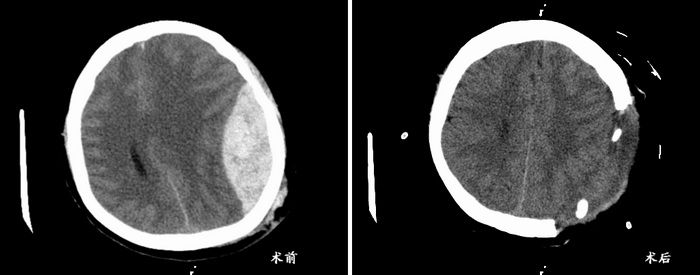

22点35分,一切保障到位后,手术开始了,麻醉、消毒、铺巾……紧张而有序,大家屏住呼吸,全神贯注。术者操作格外小心翼翼,遇到血管提前分离、烧灼,仔细止血,把已经出的血用吸引器全部回吸收一滴不剩。钻孔、铣骨瓣、吊硬膜,吸血肿、剪硬膜、探查硬膜下腔,每一个操作都迅速而熟练,术者不放弃任何一个小的出血点。零点40分,手术室里的手术接近了尾声,血肿清除完毕,放置引流,王浩副主任反复冲水确认无明确出血点后关颅,手术顺利结束,术中出血240ml。手术后的清洁袋里居然是干干净净的,放置的硬膜外引流也没有血液引流出来。经过2个多小时的手术,大家虽然都很疲惫,可心里还是充满喜悦的。术后第2天,周女士就苏醒了,言语流利,四肢活动正常,复查头部CT,血肿清除,手术效果满意。这就是神经外科在双“十一”遇到“熊猫血”,多方协作,终保患者平安康复的故事。